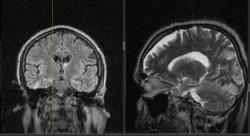

Мужчина 1964 г.р. Жалобы на нарушение памяти, снижение зрения и кратковременную потерю сознания, температура нормальная.

Я думаю что это может быть какой нибудь васкулит, либо Posterior Reversible Encephalopathy Syndrome, о чем можно думать в данном случае?

eto pres

Я представлял синдром с более выраженным изменением сигнала от белого вещества и меньшим - коры.